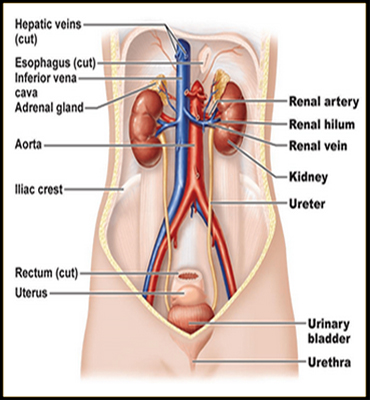

Kidney Disorders

Kidney Diseases Like :

- Kidney Stone

- Kidney Cyst

- Hydronephrosis

- High Creatinine Level

- Kidney Failure

- CKD

- Repeated Urinary Tract Infection

- Ureteric Stone